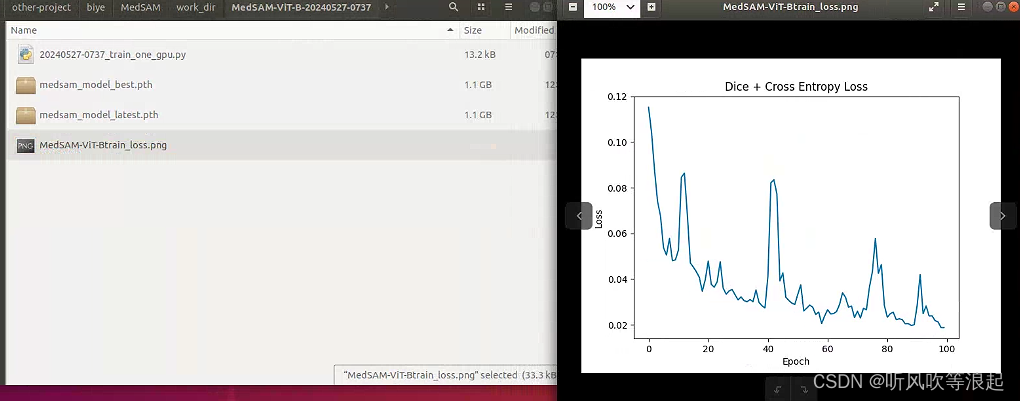

权重: